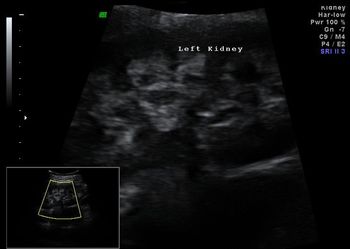

A 27-year-old pregnant patient with history of renal colic. Ultrasound showed increased echogenicity of renal pyramids. Both kidneys showed a small calculus both sides.